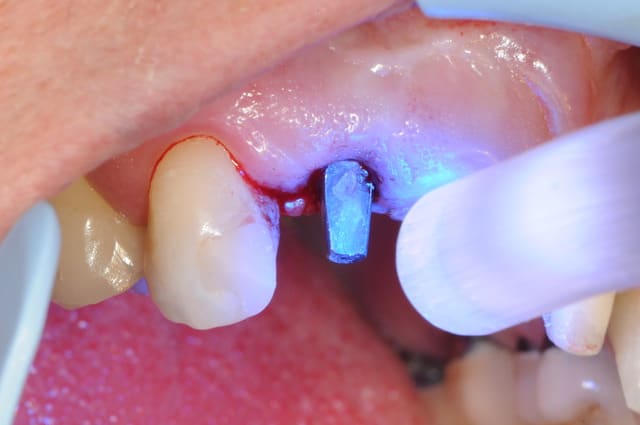

je jour J, à l'heure H, je fini par poser mon implant.

il reste même après deux mois encore des saletés (photo2)

photo

3- axe implantaire

4-5 pose implant et comblement

6 sutures ( je sais, c'est affreux des gros fils en soie!)

donc après encore 3 mois, je fais enfin la mise à jour de l'implant (un vrai bonheur avec ce système implantaire où l'on vient chercher la vis de couverture "à l'aveugle")

protection du trou d’accès avec du compo provisoire (photo5)